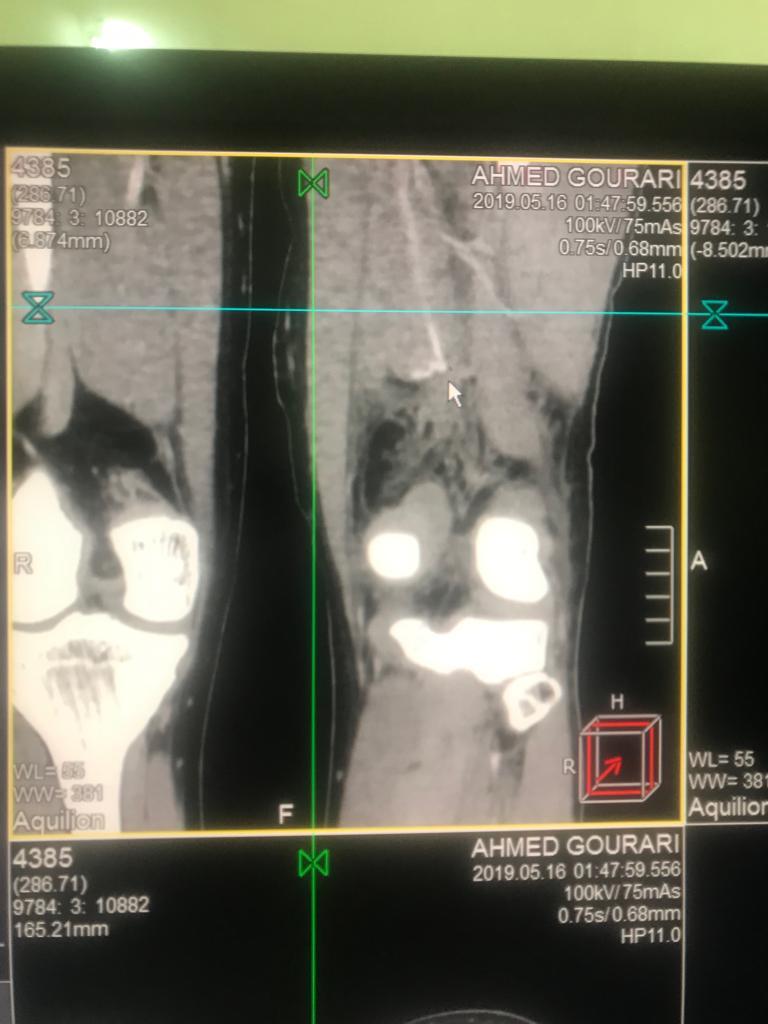

وقد أعطيت للمصاب الإسعافات والعلاجات الملائمة في العناية المركزة، وتم إجراء فحوصات بالأشعة-

السكانير- التي أكدت الإصابة الخطيرة التي ستؤدي إلى فقدان الطرف السفلي في حالة عدم التدخل الاستعجالي.